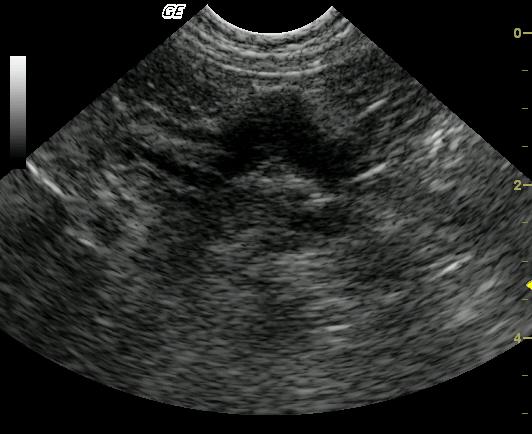

The transverse image of the stomach reveals marked focal thickening of the gastric wall extending from the ventral surface to the lesser curvature. The affected gastric wall is hypoechoic and lacks wall layering. The echogenic wedge-shaped foci noted in the near field within the thickened gastric wall may represent an area of necrosis or fibrosis. Video: Loss of detail is noted in the affected pyloric outflow tract meeting neoplastic criteria but complicated inflammatory disease may present occasionally in this manner. The lesion is focal and may be resectable.

Gastric wall mass consistent with neoplasia such as lymphosarcoma or a similar round cell tumor. Severe, focal inflammatory or granulomatous disease is considered less likely.